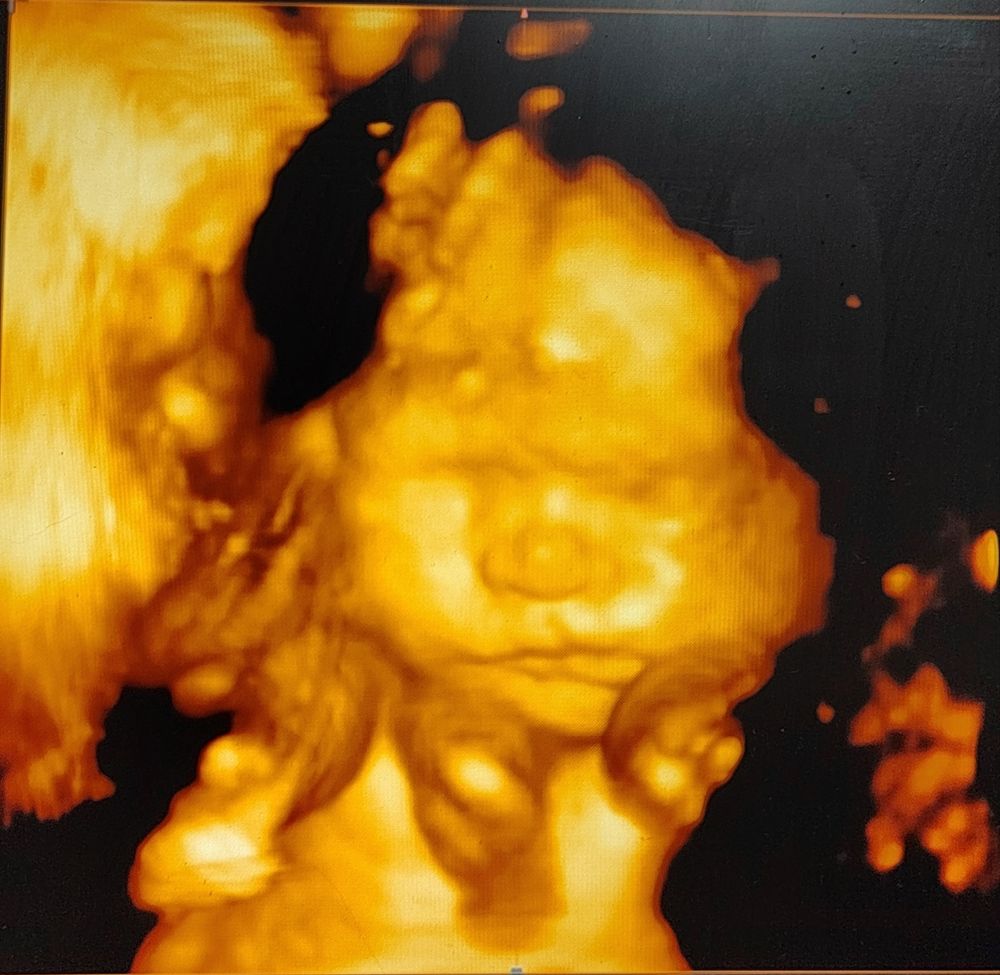

3д узи в 26+3

Наши будни, наши неделькиОказалось весёлая процедура 😁 И врач попалась очень весёлая, я в основном только на скрининги в жк ходила и в приёмнике, там обычно все сухо и по делу) и фото получились отличные 😍 интересно сравнить будет ли похож, осталось всего-то 3 месяца 😰 так быстро время пролетело

Ну и моя булка ❤️